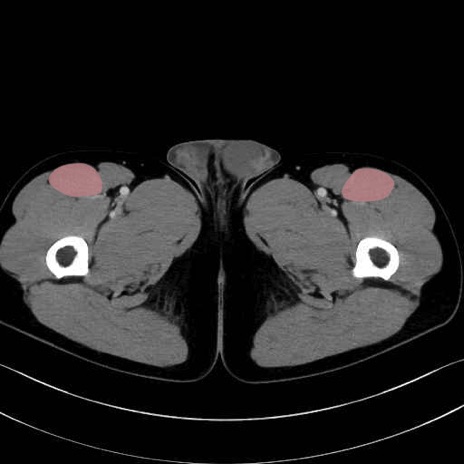

5. 大腿前面(大腿四頭筋群・伸筋群)

縫工筋 (Sartorius)

大腿直筋 (Rectus femoris)

外側広筋 (Vastus lateralis)

中間広筋 (Vastus intermedius)